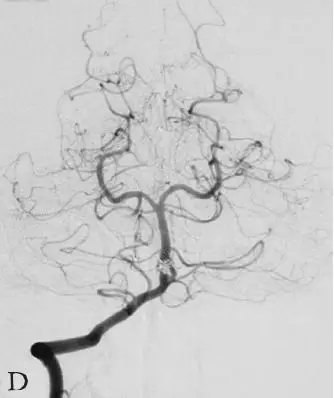

DSA:急诊行全脑血管造影提示基底动脉下段可见1枚形态不规则囊性动脉瘤(图18-3B)。三维重建后提示基底动脉下段开窗畸形,动脉瘤瘤颈位于开窗近段分叉处,瘤顶有子囊(图18-3C),动脉瘤瘤颈1.85 mm,瘤深5.45 mm,瘤宽2.77 mm。左侧椎动脉造影提示左侧椎动脉仅供血小脑后下动脉(PICA)区域,未汇入基底动脉(图18-3D)。颈内动脉造影未见明显异常。

D:左侧椎动脉造影提示左侧椎动脉发育不良,仅供血小脑后下动脉(PICA)区域。